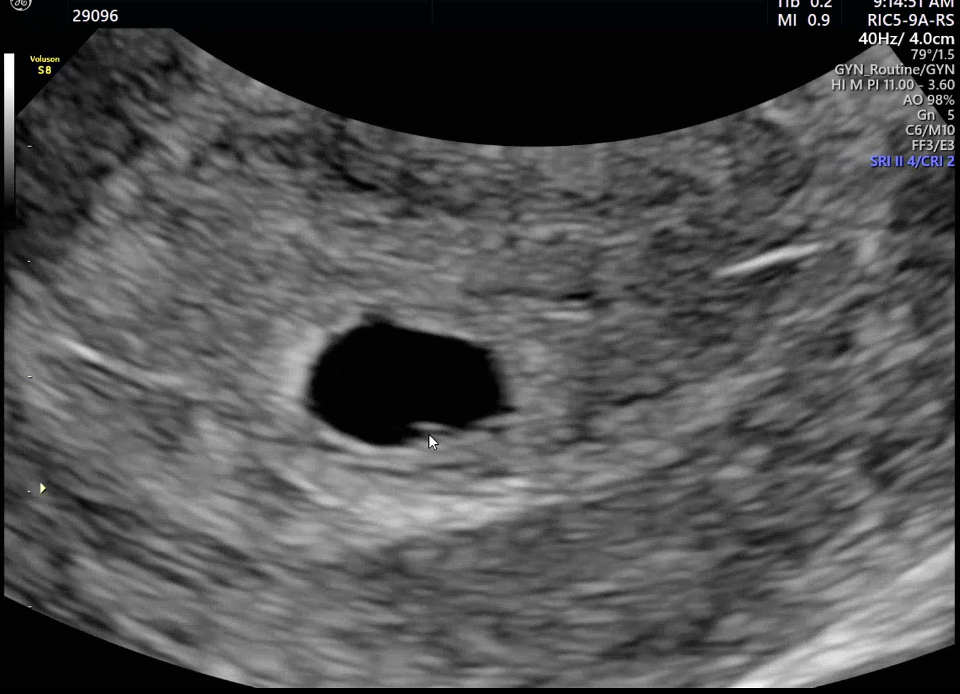

| 치료 도중 느꼈던 가장 기뻤던 순간과 절망적인 것들은 무엇인가요? 잊지 못할 경험이 있나요? | 가장 기뻤던 순간은 두 가지입니다. 1. PGT 검사에서 건강한 배아 4개가 통과되었을 때 2. 첫 시험관 시도에서 임신이 확인되었을 때 반대로 가장 절망적이었던 순간은 6주 차에 큰 출혈과 심한 복통을 겪었던 때였습니다. 하지만 다행히 잘 극복해낼 수 있었고, 오히려 그 경험이 생명의 소중함을 더 크게 느끼게 해주었습니다. |